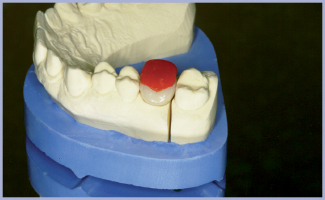

Paziente di sesso maschile di anni 36, nessuna notizia anamnestica particolarmente rilevante. La radiografia pre-operatoria dell’area edentula da riabilitare, zona 16, mostra una scarsa disponibilità ossea verticale. Si esclude un intervento di mini rialzo di seno optando per l’impiego di un impianto corto 6.5 Exacone® (fig. 1) in tecnica monofasica poiché, al momento dell’inserimento, la stabilità primaria è eccellente. Dopo cinque mesi si procede alla rimozione del tappo di guarigione, alla verifica della guarigione dei tessuti ed alla presa dell’impronta in polietere (Impregum™ 3M ESPE). Sopra il transfer si posiziona l’analogo con il suo pin. Le componenti (transfer, analogo, ecc.) che si utilizzano sopra l’impianto corto sono le stesse dell’impianto 4,1, come si evince dalle foto (figg. 3-6). Dopo aver sviluppato il modello, condizioniamo il gesso per migliorare i volumi del dente che andiamo a progettare, non solo per una questione estetica ma anche per un maggior comfort per il paziente (figg. 7, 8). Si procede alla digitalizzazione del modello master tramite scansione con dispositivo Inlab Sirona (fig. 9).

Grazie al software CAD andiamo a progettare la forma e i volumi finali per poi ricavarne una struttura anatomica che sia di sostegno alla ceramica in modo ottimale (figg. 10, 11). A questo punto spediamo via internet il file in questione (figg. 12, 13) al centro Infinident Sirona dove inizieranno subito la lavorazione. Dopo solo due giorni dall’invio, il progetto trasformato in manufatto viene recapitato in laboratorio. Il manufatto è realizzato in lega cromo-cobalto tramite un processo di laser sintering (SLS). Il suo aspetto è solo apparentemente poroso (fig. 14) mentre il suo adattamento al moncone MultiTech è immediato (fig. 15) grazie alla precisione della tecnica di produzione SLS. Una leggera rifinitura mette subito in evidenza l’ottima qualità della lega CrCo (figg. 16-18). Vi si applica sopra prima l’opaco (fig. 19) e poi la ceramica (fig. 20) per la realizzazione della corona definitiva (figg. 21, 22, 24). Poiché si prevede che la corona sarà cementata extraoralmente sul moncone dopo aver eseguito la prova in bocca, si realizza un jig (fig. 23) per l’attivazione della connessione conometrica e nello stesso tempo proteggere la ceramica. Dopo aver verificato in bocca la corona sia per la forma, i punti di contatto e il colore, si effettua la cementazione extraorale sfruttando come supporto il manico per monconi (figg. 25, 26).

- Fig. 8 – Modello con moncone MultiTech e condizionamento gengivale